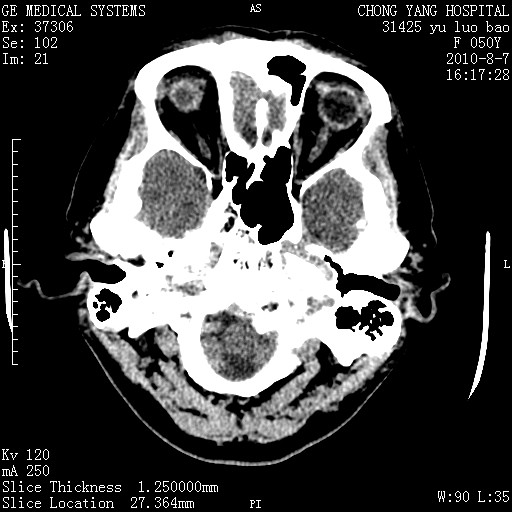

标题: CT28285:听力下降一年,头昏。 [打印本页]

标题: CT28285:听力下降一年,头昏。

右侧桥小脑角区占位--听神经瘤,建议增强或mri检查。

右侧桥小脑角去等密度占位,右侧内听道扩大、骨质吸收,考虑:右侧听神经瘤,建议增强检查。

右侧内听道扩大、骨质吸收,中脑受压左移,考虑:右侧听神经瘤,建议增强检查。支持!

右侧桥小脑角区等密度占位,内耳道扩大,听神经瘤